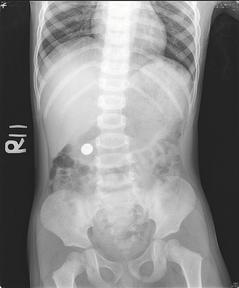

台中慈济医院小儿科医师李宇正先为男童做X光检查,果然看到圆形电池就卡在男童胃部,第二天再照X光,看到电池已掉到大肠,第叁天随粪便排出,但家长仍担心日后会影响儿子健康。

台中叁岁男童误吞超商的玩具内电池,做X光检查,果然看到圆形电池就卡在男童胃部。 照/台中慈济医院提供